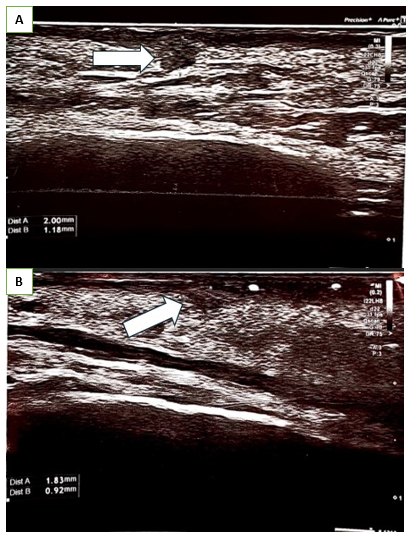

On days 5 and 7 following the procedure, the patients reported the persistence of micro papules in the periorbital areas. The papules were firm, non-painful, with minimal or no visible inflammatory reaction in the surrounding tissues. The patients A and B underwent follow-up consultations, massage and PRP (platelet-rich plasma) autologous injections were performed (Figure 1) (Figure 4). During consultation the status of the papules was evaluated using physical assessment with visual and palpatory control. The patients A and B underwent ultrasonographic examination on 13th day after collagen injection with a high-resolution 22 MHz Canon probe to determine the depth of the micro papules, which concluded the presence of the papules in subdermal layer. (Figure 2) (Figure 5A, B). The patient A underwent a tissue histology examination and 14th day after collagen injection to assess the nature of the papules, the reaction of the surrounding tissue, and the nature of the inflammation, which concluded that the papules are collagen collection without perifocal inflammation (Figure 3). Follow-up consultation was performed on day 28 after injection which concluded resolution of the symptoms, no visible or palpable papules were observed (Figure 5A & 5B).

Figure 2 Ultrasonography of Patient A right eyelid skin, performed using a Canon Hockey Stick 22 MHz probe, revealed hypoechoic collagen aggregates closely adhering to the dermal layer.

Figure 5 Ultrasonography of Patient B of right eyelid skin, performed using a Canon Hockey Stick 22 MHz probe, revealed hypoechoic collagen aggregates closely adhering to the dermal layer.